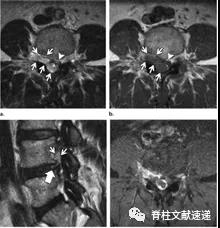

图注:硬膜内腰椎间盘突出

图注:42岁男性,有L4/5椎间盘切除手术史,出现急性马尾综合征。术中见硬脑膜上有小开口,硬膜内部分钙化椎间盘组织。